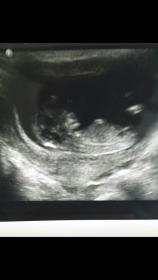

12 weeks 1 day

Went for the NT scan and I kept seeing a straight forked nub but whenever it was very clear the tech moved the transducer. She gave me a couple of very blurry pics but I did get this one pic where I believe the nub is visible. It looks boyish to me but then I'm wondering if the spine is curved up which might make it girly. What do you guys think?

Slight pink lean because baby's back looks curled so hard to tell plus it's on the early side for nub guesses.

It's too early for me to guess, but beautiful baby!!